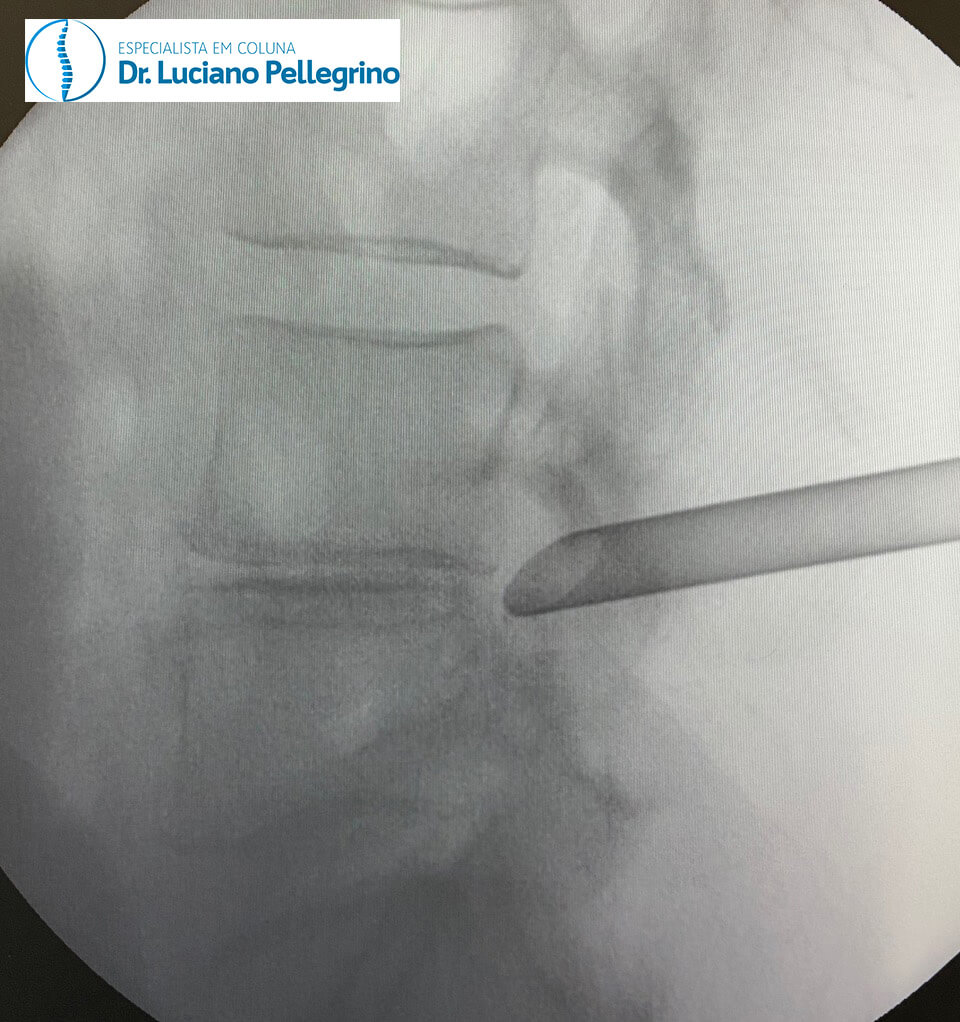

O uso da técnica da endoscopia de coluna se dá através do uso de uma pequena câmera e pequenos instrumentos cirúrgicos (para inserirmos a cânula no local correto antes de entrar com o endoscópio, fazemos uso da radioscopia, como indicado nas figuras abaixo).

Em grande parte dos casos, é realizada uma incisão mínima (cerca de 8 milímetros) na coluna do paciente, com o mesmo sob anestesia geral ou sedação.

A magnificação obtida pela ótica da microcâmera permite a visualização das estruturas anatômicas com alta precisão e com muito menos sangramento do que a cirurgia convencional, pois há a infusão contínua de soro fisiológico pela cânula.